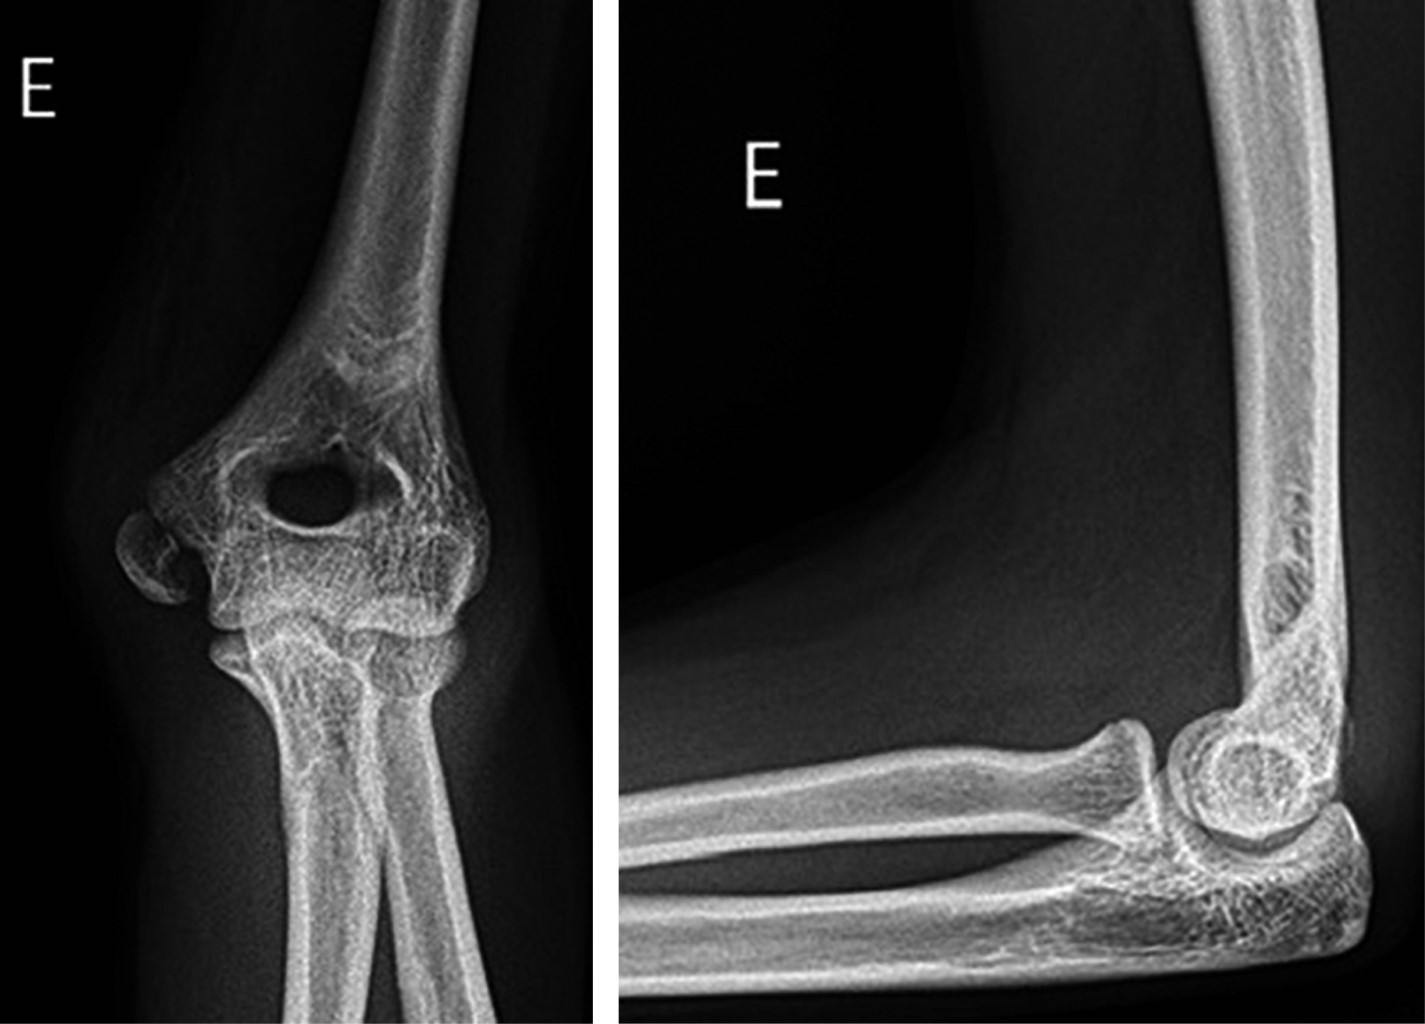

Surgical treatment of the medial epicondyle fracture of the humerus using the ''Inside-out'' technique. Description of the technique and results

Introduction: the "Inside-out" technique is one of the options for medial epicondyle fracture fixation of the humerus. It involves preparing the fixation from the internal portion of the fracture to the external portion. Then, the fracture is fixed with a cannulated screw from the external to the internal portion. This study aims to describe our experience with this technique, its outcomes, and its complications. Material and methods: this is a retrospective observational study describing a series of cases treated with the "Inside-out" technique for medial epicondyle fracture fixation from 2020 to 2024. We evaluated demographic data, follow-up duration, intraoperative events, postoperative complications, and functional outcomes. Results: we analyzed 21 patients, 61.9% of whom were male, with a mean age of 13 years and a mean follow-up period of 19 months. Among these, 71.4% had fractures in the right upper limb, with the most prevalent trauma mechanism being a ground-level fall. No open fractures were observed. A total of 38% had dislocated elbows with an incarcerated medial epicondyle, and one patient had an associated fracture. There were no intraoperative complications. One patient had a 5-degree extension limitation, all fractures achieved consolidation, and no postoperative neurological injuries or valgus instability were observed after fixation. Four patients reported discomfort at the site of the screw head insertion, and one patient complained of a hypertrophic scar. The functional assessment using the QuickDASH score yielded an average of 1.1. Conclusion: the "Inside-out" technique provided secure fixation of the medial epicondyle, preventing its fragmentation, ensuring fracture consolidation, allowing early mobility, and resulting in minimal complications.

Figure 1